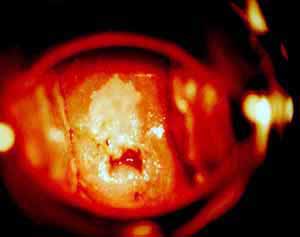

Κολποσκοπικές εικονες για τις αναγκες του forum.